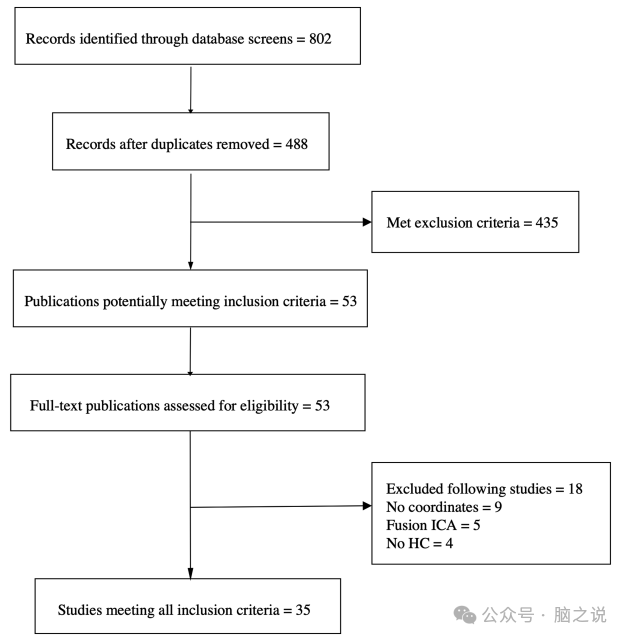

在MOOSE(观察性流行病学研究指南的荟萃分析)之后,我们在PubMed、Scopus和Web of Science中对2022年1月之前发表的文献进行了一项无任何语言限制的系统研究。组合使用以下关键词:(精神病性障碍或精神病性或精神病性或精神分裂症)AND (first-episode OR first episode) AND (fMRI OR MRI, functional OR functional MRI OR functional MRI OR MRI, functional) AND (connectivity OR resting state OR resting state OR AIFF OR fAIFF OR ReHo)。然后对相关综述和荟萃分析的参考文献列表进行检查,以确定是否有其他相关研究。最初的搜索产生了802篇文章。对纳入文献的摘要和研究对象的纳入标准进行筛选,剔除重复,最终筛选出53篇文献进行全文阅读。如果无法获得全文,则与作者直接联系。我们纳入了符合以下标准的论文:(a)经过同行评议的原创论文;(b)患者符合精神分裂症谱系精神病(精神分裂症、分裂情感性和精神分裂症样障碍)和情感性精神病(具有精神病性特征的双相障碍和重性抑郁症)的标准化诊断标准(DSM, ICD);(c)明确报告患者的病程≤5年;(d) Talairach (TAL)或蒙特利尔神经研究所(MNI)峰效应坐标在FEP和HC之间有显著差异。排除标准如下:(a)没有使用低频振幅、低频振幅或局部一致性(ReHo)技术研究自发性脑活动;(b)他们使用ROI分析;(c)即使联系了作者,也无法获得峰值坐标。共纳入35篇文献(遴选过程见图1)。由于Jiang等、Cui等、Li等和Fang等的文章报告了来自两个或多个队列的数据,因此在荟萃分析中,它们被视为独立的研究。此外,报告多个测量指标的文章被认为是ReHo和AIFF/fAIFF分析的两个不同的研究。我们还根据年龄对荟萃分析进行了分层:如果研究中的两个样本的平均年龄≤18岁,则该人群被归类为青少年FEP,否则被归类为成人FEP。没有一项研究报告了熟悉的精神病史的细节。所有研究均采用影像学方法学质量评估清单进行评估(见补充材料)。

图1 PRISMA流程图用于FEP中影像学文章的荟萃分析。每一篇选定的文章可以包括多个体积测量值,这些测量值被视为单独的研究。因此,研究的总和大于所选的文章。